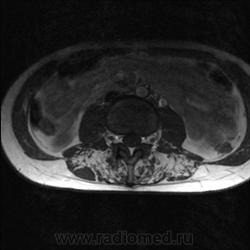

Пациентка 25 лет обратилась к неврологу с жалобами на слабость, изменение походки. Раньше не обследовалась.

каким уровням соответствуют аксиальные срезы?

obada, так точно! Срезы в данном случае значения не имеют, т.к. патологии межпозвонковых дисков нет, а мышцы одинаково выглядят на всем протяжении.

Я специально сделал изображения потемнее, чтобы выделить патологию (жировую дегенерацию) именно мышечной ткани.

Гм, как это я пропустил эту публикацию. Поясничные мышцы замещены жировой тканью; т.е. Они выглядят "белыми" на Т1 и Т2, в последовательности с подавлением жира, соответственно сигнал уходит; и они "тёмные". Такую картину я видел у пожилых, иногда у пациентов после операции на позвоночнике. По поводу болезни Штейнерта, должна быть клиника, изменения и гипотония/атония мышц других локализаций. На основании только МРТ ПОП не совсем убедительно. Вот небольшая ознакомительная статейка.